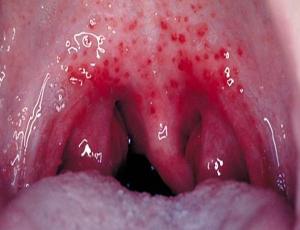

У взрослых отличительным симптомом герпетической ангины является появление на задней стенке глотки, миндалинах, мягком нёбе, язычке, передней части ротовой полости мелких красноватых пузырьков с серозным (светлым, не мутным) содержимым, напоминающих герпетические поражения.

Со временем пятнышки образуют язвы, что доставляет заболевшему большие неудобства, поскольку они сильно болят. Потом язвочки перерастают в пузырьки, которые имеют серозное наполнение. Они лопаются и образуют изъязвления. Как правило, их насчитывают от 5 до 20 штук. В некоторых случаях пузырьки могут слиться, что приводит к достаточно крупным поражениям на слизистых горла и ротовой полости.

- Покраснение слизистых оболочек анатомических образований полости рта в течение суток (миндалин, небных душек, мягкого неба и язычка).

- Появление папул на слизистой оболочки полости рта, через 24 часа после покраснения.

- В дальнейшем формирование пузырьков (в течение 48 часов), которые после вскрытия оставляют афтозные язвочки.

- Формирование в тяжелых случаях эрозивных поражений, после слияния афт.

Герпетическая ангина: фото

Как выглядит данное заболевание у детей и взрослых, представляет к просмотру подробные фото: